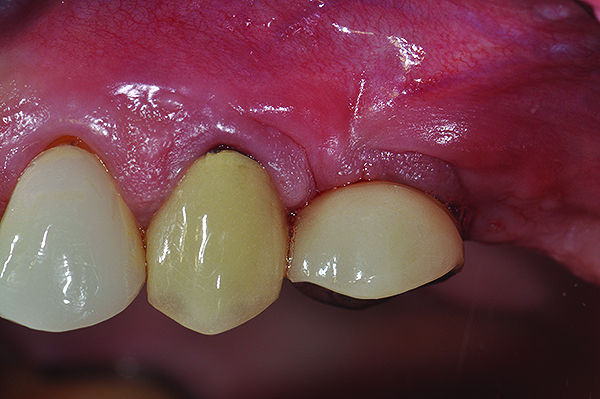

Fig 1. Clinical view of maxillary left lateral incisor implant in a healthy 48-year-old man. The swelling in the tissue surrounding this implant also bled on probing with depths up to 8 mm and exhibited purulence. The implant has been present for 14 years.

Figure 1

Fig 2. Radiograph of this same area. Note that there is no indication of bone loss and a long abutment collar. Hence, the diagnosis of peri-implant mucositis is given.

Figure 2